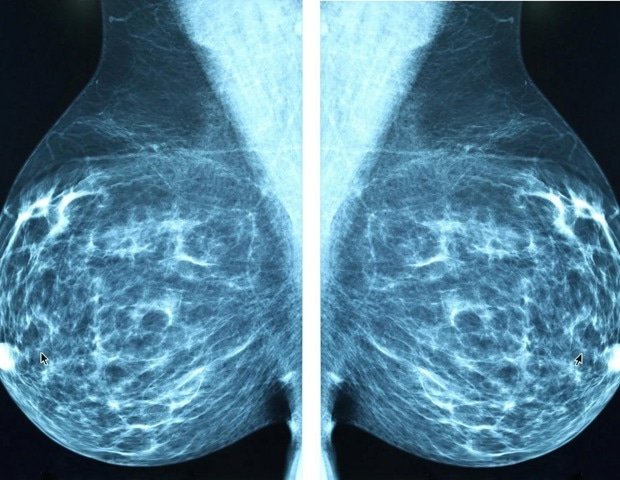

Breast cancer is one of the most common malignancies worldwide, and mutations in the PI3K/AKT/mTOR (PAM) signaling pathway are prevalent during its development. Of these, PIK3CA Mutations play a pivotal role in guiding treatments with PI3K inhibitors, which have shown promising antitumor effects. However, traditional molecular assays such as polymerase chain reaction (PCR) and next generation sequencing (NGS) require expensive infrastructure and are not always feasible in routine clinical practice. Deep learning models have emerged as a cost-effective solution to predict important mutations from digital pathology images. Nevertheless, most existing models rely on single-modal data and often lack the complementary insights that structured clinical data can provide. These challenges highlight the need for improved predictive models.

Research published in (DOI: 10.20892/j.issn.2095-3941.2025.0771) Cancer biology and medicine In February 2026, a team of researchers from the 4th Hospital of Hebei Medical University developed a new multimodal artificial intelligence (AI) model for prediction. PIK3CA Mutations in breast cancer. The model integrates deep learning-based analysis of whole-slide pathology images with structured clinical data such as age, molecular subtype, and lymph node status. This study utilized data from The Cancer Genome Atlas (TCGA) and three external clinical cohorts to demonstrate the robustness of this model and its potential as an accessible alternative to molecular testing in diverse clinical settings.

A multimodal framework for research, known as multimodal PIK3CA The model (MPM) combines two components: a histopathological model and a clinical model. The histopathology model uses a transformer-based pre-trained encoder (H-optimus-0) and a clustered constrained attention multiple instance learning classifier (CLAM-SB) to process high-resolution whole slide images. This model identifies morphological features associated with: PIK3CA mutation. Clinical models based on XGBoost analyze structured clinical data to predict mutational status. Both models generate independent probabilistic predictions that are fused using a decision-level late fusion strategy to generate the final mutation status prediction. MPM outperformed a single-modality model, achieving an area under the curve (AUC) of 0.745 in internal testing and stable performance (0.695 to 0.680 AUC) across external validation datasets. Inclusion of clinical variables such as molecular subtypes and lymph node status improved the predictive accuracy of the model, highlighting the importance of combining morphological and clinical data. This study also demonstrated the ability of this model to generalize across a diverse cohort, making it a promising tool for real-world clinical applications.